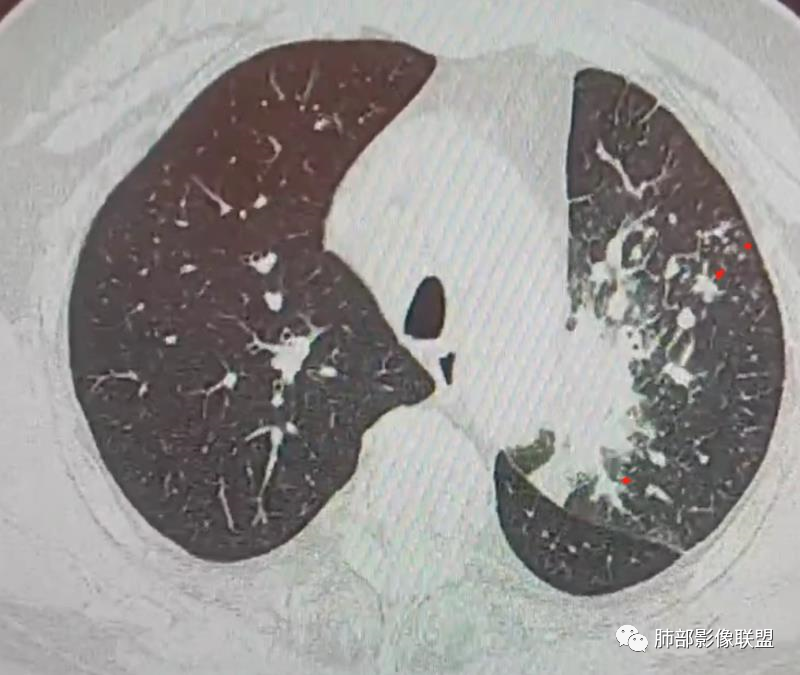

三、影像表现:左肺上叶多发片状高密度影,散在,边缘模糊,支气管壁稍增厚,中轴间质、小叶间隔增厚、有结节感,左肺上叶前段病灶可见胸膜增厚,部分小支气管不能分辨;右肺上叶后段混合磨玻璃结节,边界清,邻近胸膜凹陷;纵膈淋巴结肿大;心包增厚;左侧少量胸水。此外,扫及右侧胸腔内甲状腺肿;左侧肩胛骨旁肌群内脂肪瘤。

四、综合分析:老年男性,以咳嗽咳痰为主要临床表现,无发热,白细胞正常,影像表现为左肺上叶片影,前段结节影、胸膜增厚、部分小支气管不能分辨。左肺上叶中轴间质增厚、小叶间隔增厚、结节感,肺门纵隔见肿大淋巴结,尽管肺部病病灶边缘特征不典型,但高度疑及癌性淋巴管炎这一“次生灾害”却具有相当重要提示意义,而肺癌中最常伴癌淋的就包括腺癌。右肺上叶后段混合磨玻璃结节,边界清楚,张力明显,具有一定特征性,高度指向浸润性腺癌。这对于左肺病灶具有一定程度“助攻”效应。总体而言,本例左肺病灶的诊断关键点在于判断出癌性淋巴管炎。癌性淋巴管炎的结节在外围间质多见,小叶间隔可呈串珠状、结节状增厚,由于出血及水肿,小叶间隔增厚较明显,或呈不规则增厚。有的肺小叶呈多角状阵列。常合并胸水。

肺癌性淋巴管炎(PLC)是肺内、外肿瘤肺转移的一种特殊类型,以 转移癌细胞在淋巴管内弥漫性生长为特征,占肺内转移瘤的6.8%。癌 细胞可播散至肺淋巴管及血管,最终因呼吸衰竭和肺源性心脏病而导致病死亡。临床症状主要为干咳、憋气、体重减轻及低氧血症。本病预后极差,50%~85%的患者生存期3~6个月,临床诊断较困难,常误诊为其它肺间质性病变。 PLC的主要CT征像当中肺纹理异常改变最常见,肺纹理不规则增多、增粗并多发微小结节状更形象解释癌细胞在淋巴管内生长成结节及周围间质增生,导致淋巴管通道堵塞,远处淋巴液回流受阻,通过其它细小交通回流,从而导致肺纹理增粗增多,是PLC较有特征性CT征象,其它疾病所导致的肺纹理增多增粗一般较规则,可为粗细不均或受牵拉变形却极少出现结节状增粗并呈串珠状排列。小叶间隔不规则增厚并多发小结节也是因为小叶间隔淋巴管癌细胞生长及淋巴管通道受阻扩张所致,虽然小叶间隔结节状增粗,但小叶结构不变形是PLC较为特征的CT表现,肺纤维化、 肺水肿、肺胶原病及结节病等肺间质性病变中较少见小叶间隔结节状增粗,而且它们一般导致肺小叶结构变形。肺小叶内间质增生及(或)核心小结节无明显特异性,其表现与特发性肺纤维化、 尘肺及结缔组织病及其它可导致肺间质性纤维化疾病的小叶内间质增厚相类似。PLC导致的胸膜增厚也有一定特征,一般累及胸膜范围较广,程度轻,密度较淡, 部分呈花边样改变,以叶间胸膜较常见,绝大部分病例叶间胸膜受累呈轻度增厚并沿表面排列多发微小结节,伴随PLC其它征象,未见单独存在。肺内结节及 (或)小斑片状实变影无特异性, 与肺结核、炎症、肺血行转移瘤及类风湿等结缔组织病的肺部表现相似,也可能为合并血行转移及肺部感染。纵膈及肺门淋巴结肿大、胸腔及心包积液均无特异性,曾有文献报道,单侧叶间裂积液对PLC的诊断有相对特异性, 因单侧的叶间裂积液主要是由于胸膜下淋巴管堵塞,淋巴回流受 阻所致,可提示PLC的存在。

综合上述,肺纹理不规则增粗并多发微小结节、肺小叶间隔不规则增厚并多发微小结节、轻度增厚的胸膜并多发微小结节对诊断PLC具有重要意义,三者征像同时存在时,结合肿瘤病史及临床症状, 基本可以明确诊断PLC。